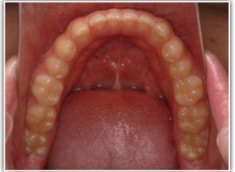

開咬(かいこう:オープンバイト)ケース

治療法:表の矯正(T21ブラケット)

(インプラントアンカーや外科矯正は行わず、エラスティックと機能訓練のみ)

治療後(2年2ヶ月後)